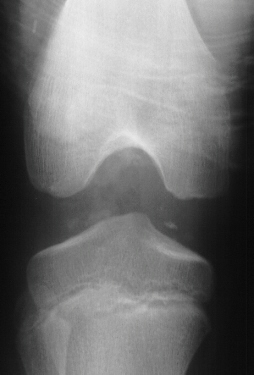

AP, lateral and obliques of the left knee showed an effusion with multiple radiodense bodies that were felt to be intraartictilar . No fractures or dislocations were evident. Comparison views of the right knee were unremarkable.

Evidence on imaging studies depends on the stage of disease. Until the loose bodies are ossified or calcified they may be radiographically invisible. This often leads to an unfortunate delay in treatment.